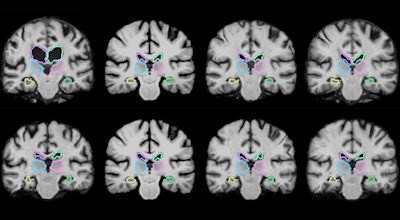

In contrast, the investigators' machine-learning algorithm, VoxelMorph, is capable of completing image registration very quickly; it was able to register 250 brain MRI scans in one to two minutes with a typical computer and in less than a second with a computer that had a state-of-the-art graphics processing unit (GPU).

The key to this high-speed registration was the extensive training the researchers had the machine-learning algorithm undergo. They fed VoxelMorph 7,000 publicly available brain MRI scans from which the algorithm was able to cull information about various groups of voxels and calculate optimized parameters that could be applied to any pair of scans. VoxelMorph's convolutional neural network (CNN) used a mathematical function to calculate the ideal alignment increasingly more quickly after each set of training scans.